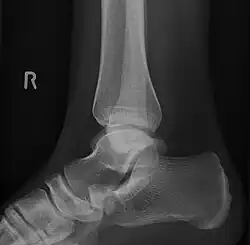

-

From left to right: Type 1, 2 and 3 -

Lateral projection of type 2 -

Type 2 -